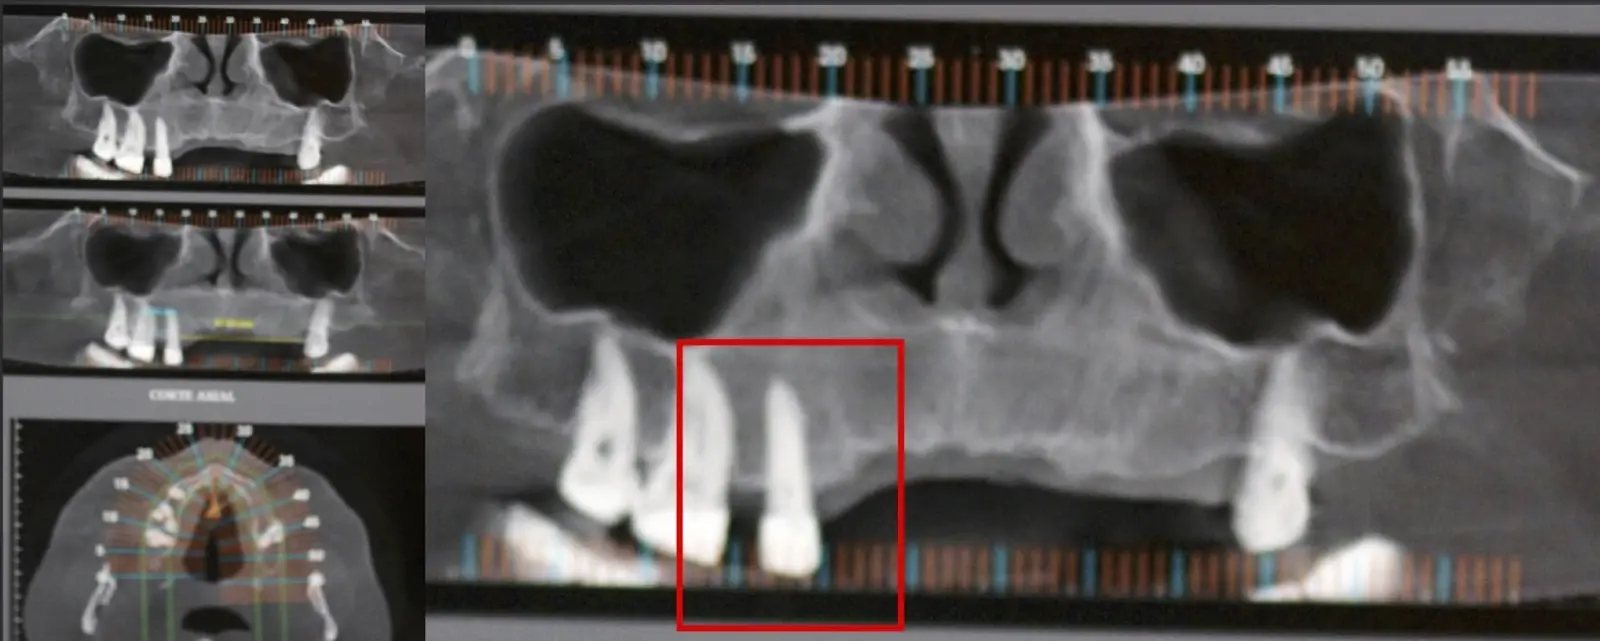

El origen puede ser bacteriano (colonias bacterianas persistentes4, patología periodontal asociada5, reinfecciones por falta de sellado coronal), mecánico (preparación deficiente, fractura de instrumentos, fracturas radiculares6, extravasación de material de obturación7 con ó sin compromiso de estructuras vecinas) y anatómico (conductos accesorios poco permeables o calcificados)8 (Figuras 1 - 4).

Figura 1. Tomografía cone beam en la que se observa la pieza 1.4 aparentemente normal, sin signos de patologías.

Figura 2. Exodoncia de la pieza 1.4 indicada como parte de una planificación de implantes dentales.

Figura 3. Concrescencia a nivel apical en la pieza extraída.

Figura 4. El mayor aumento de la concrescencia es observa a nivel apical.